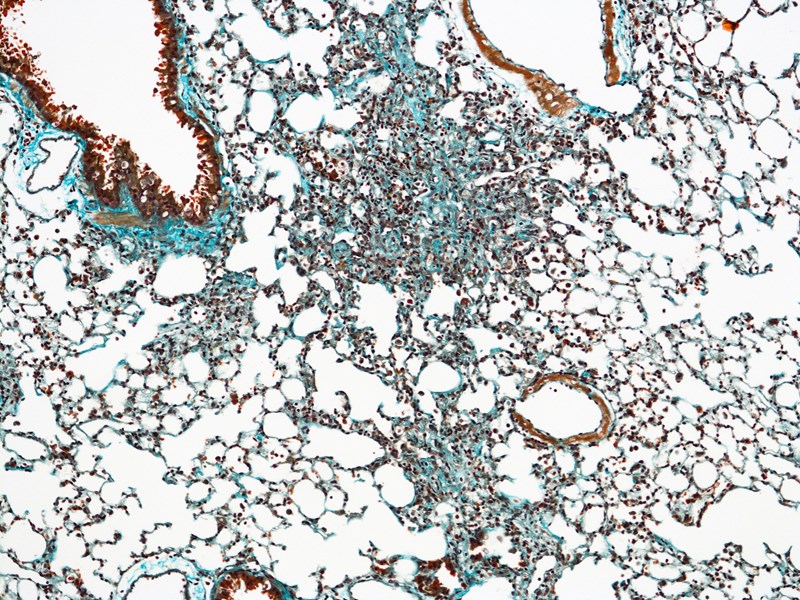

Lung fibrosis is caused by more than 100 different types of lung disease and affects millions of people worldwide.

Idiopathic pulmonary fibrosis (IPF) is a specific and aggressive form of lung disease that has no cure and a similar life expectancy as lung cancer (20% survival over 5-years).

Two recently approved anti-fibrotic drugs for IPF, pirfenidone and nintedanib, can slow down the progressive loss of patient’s lung function.

Novel and more effective medicines are urgently needed for IPF.